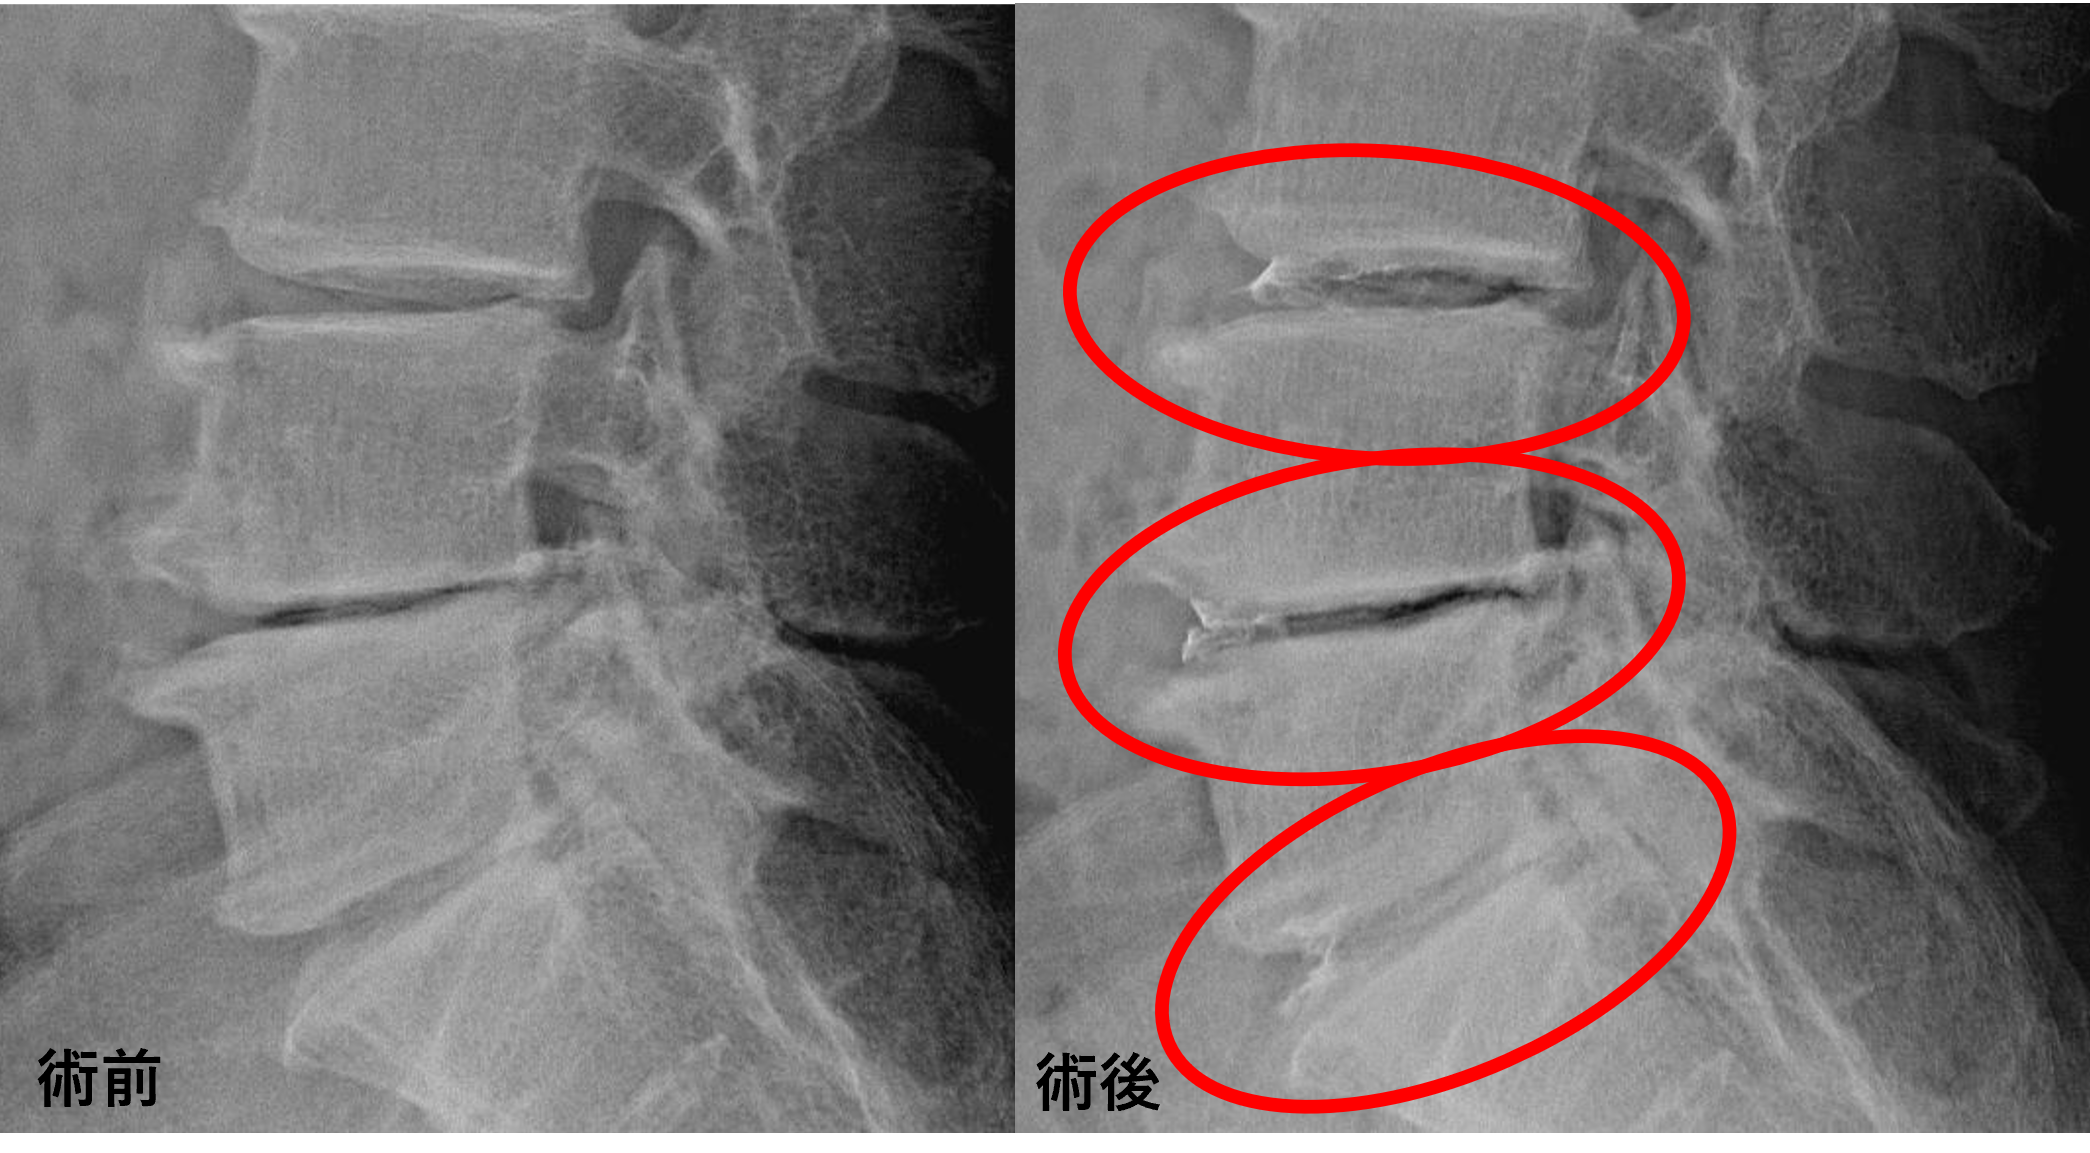

画像及び所見について

- L3/4、4/5、5/s – 椎間板変性、膨隆、椎間孔狭窄

以上のことが画像上認められました。

L3/4、4/5、5/sの椎間板所見による脊柱管の圧排が、症状の原因の可能性が高い。

患者様と相談の元、L3/4、4/5、5/sにセルゲル法を施行